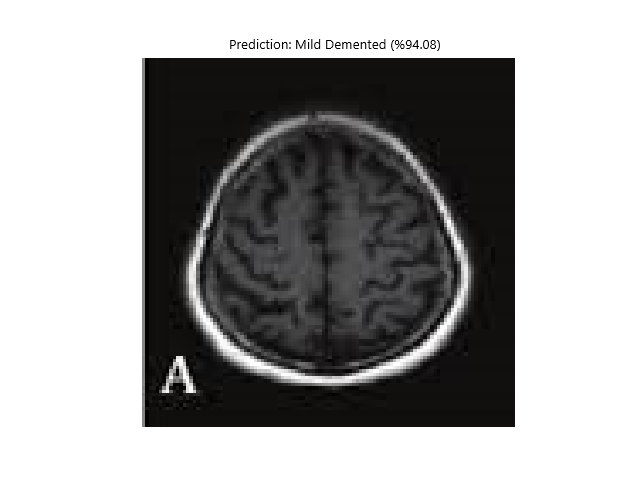

def show_image_with_prediction(image_path, prediction, confidence, class_names):

image = Image.open(image_path)

plt.imshow(image)

plt.title(f"Tahmin: {class_names[prediction]} (%{confidence * 100:.2f})")

plt.axis('off')

plt.show()

def show_image_with_prediction(image_path, prediction, confidence, class_names):

image = Image.open(image_path)

plt.imshow(image)

plt.title(f"Prediction: {class_names[prediction]} (%{confidence * 100:.2f})")

plt.axis('off')

plt.show()

- Vbai-1.0 Dementia => (Accuracy rate at least in all probability = 90%) (DEMENTIA STATES)